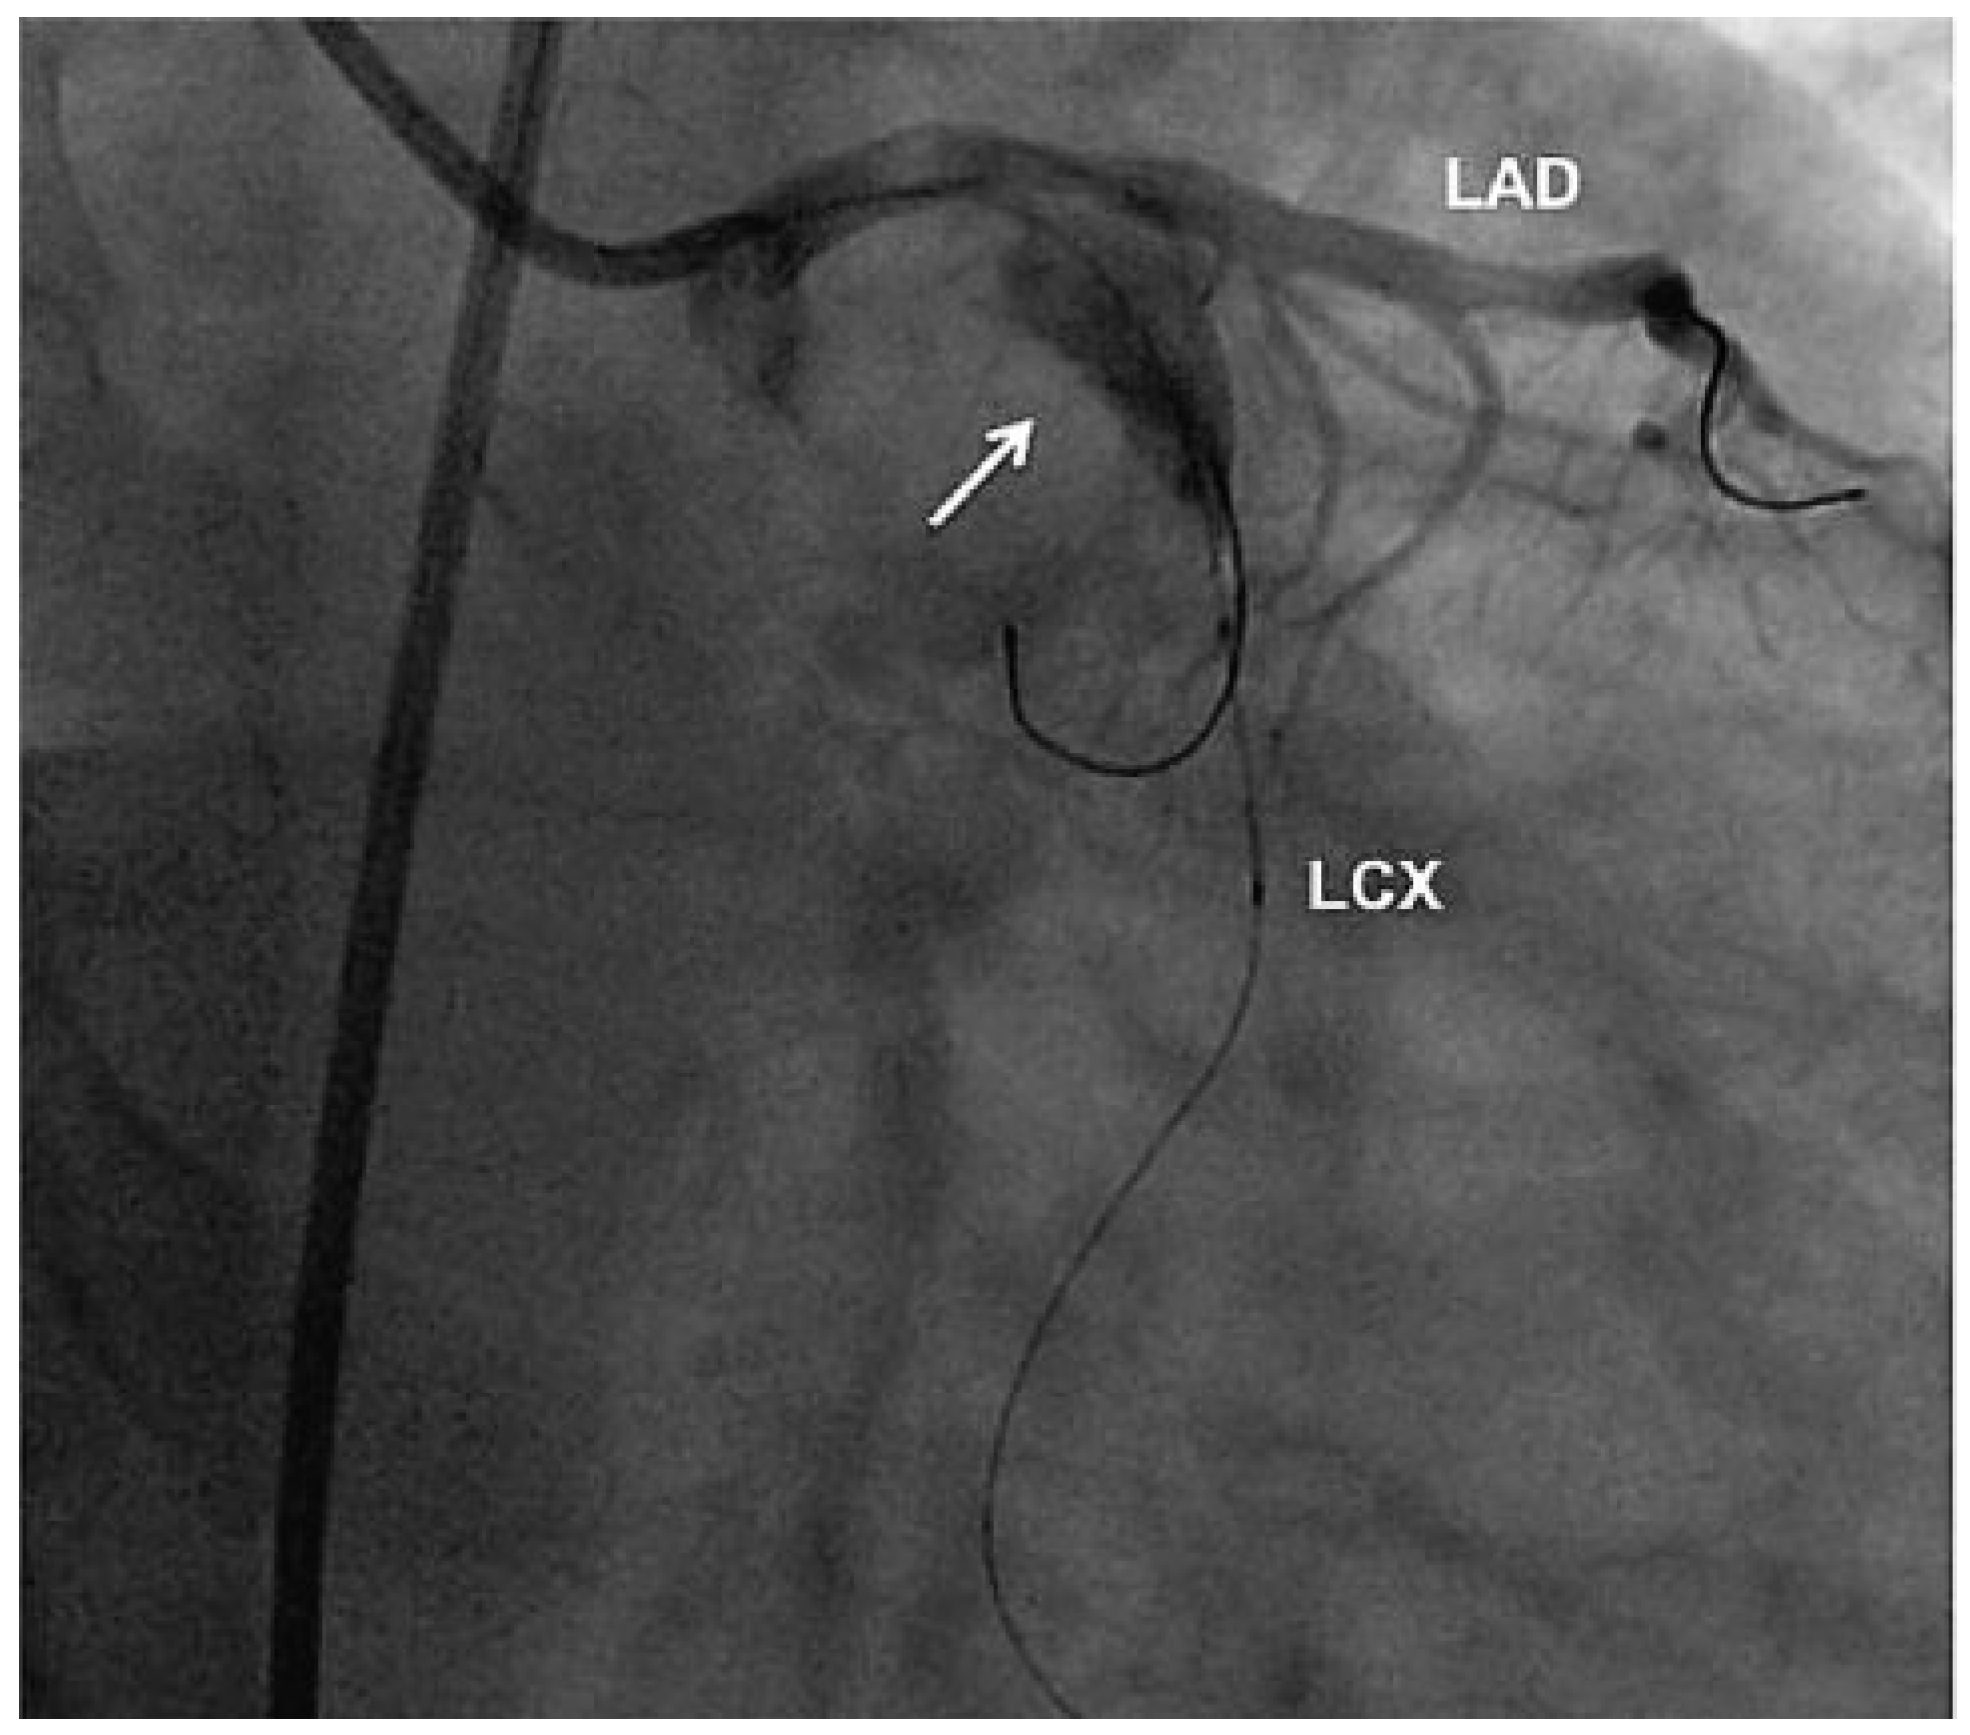

Aneurysm of the Left Circumflex Coronary Artery